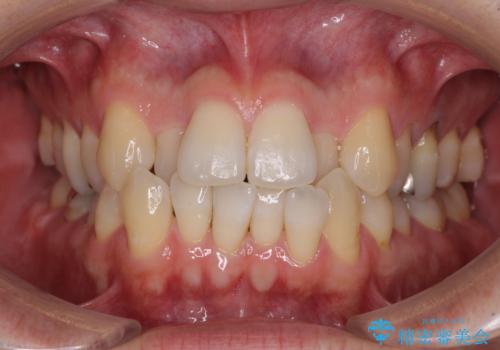

前歯のクロスバイト 目立たないワイヤー装置で矯正治療

- 前歯のクロスバイトを改善したいとのことで来院された患者様です。

マウスピース矯正では前歯の神経への負担が大きいことを懸念され、ワイヤー装置による矯正治療を行うこととしました。

舌の突出癖が認められたため、デコボコ改善に伴い前歯が前突する可能性があったため、舌のトレーニングをしっかりと行うよう指導しながら治療を進めることとしました。